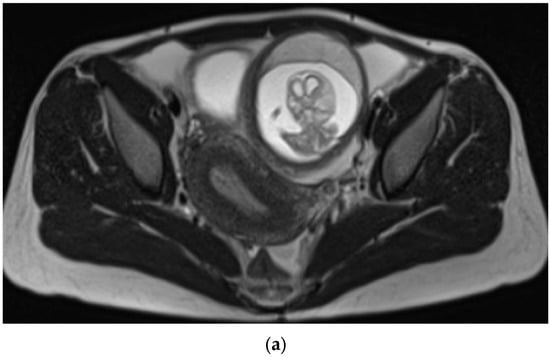

Figure 1.

A 33-year-old female presented with diffuse abdominal pain. Transverse ultrasound of the pelvis through the level of the uterus demonstrating gestational sac outside of the uterus and free pelvic fluid. Estimated live extrauterine gestational age of 13 weeks 6 days +/− 1 week 2 days. It is unclear whether the ectopic pregnancy is located within the left fallopian tube or involves the left ovary.